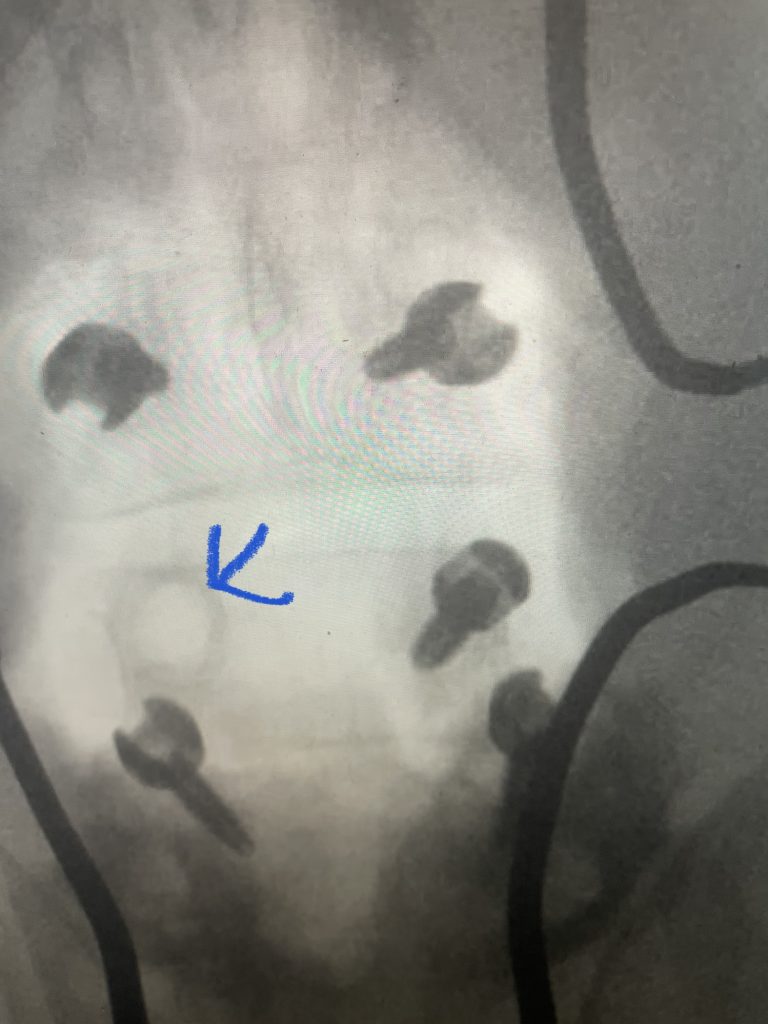

Fig 7: Intraoperative fluoroscopic AP image of the new construct from L3-5. Note the very large lucency around prior L4 screw

The patient also had a retrolisthesis at L3-4 with mild stenosis. It was also noted that he had lucencies around the L4 screws, suggesting a pseudoarthrosis at L4-5. which is a lack of bony fusion (Fig 6). Patient was had failed conservative management and was taken to the operating room where his construct was explored. There was a complete lack of bony fusion mass between L4 and L5 and the screws were loose. Interestingly the L5-S1 region had a solid bony fusion where we had used BMP, but the L4-5 region did not. We removed the construct and removed the remnant of L4 lamina and the inferior processes and decompressed from L3 to to L5, decompressing well the L4 and L5 nerve roots. We placed new instrumentation from L3-5 with the use of BMP which was discussed with the patient prior to surgery (Fig 7). We also felt it was necessary because of the failure of the fusion. Post operatively the patient had an uneventful course with significant improvement of his prior symptoms.